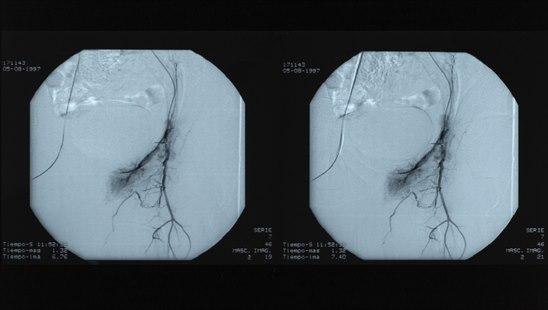

Angiografi som viser trangt parti i arterieAngiografi er en røntgenundersøkelse av blodårer. Større blodårer deles i to grupper:

Angiografi kan derfor grovt inndeles i arteriografi og venografi, avhengig av hvilke kar som undersøkes. For å kunne fremstille en blodåre på røntgen, må det sprøytes kontrastvæske inn i åren. Kontrasten gjør blodåren synlig og man kan granske om det foreligger forandringer i åren.

Undersøkelsen gjør det mulig å påvise skader, forsnevringer, blokkeringer, utposninger (aneurismer) på årene, og viser også blodtilførselen til de organene eller områdene blodårene forsyner. I mange tilfeller vil de være bedre å bruke andre undersøkelsesmetoder som CT eller MR angiografi eller ultralyd med Doppler.

Det vanligste funnet ved arteriografi er trange arterier, arteriestenose, som følge av åreforkalkning (atherosklerose). I noen tilfeller finner man at årene er helt tette. Ved behov for ytterligere undersøkelser overveier man å gjøre andre former for undersøkelser, ofte CT, MR eller ultralyd.